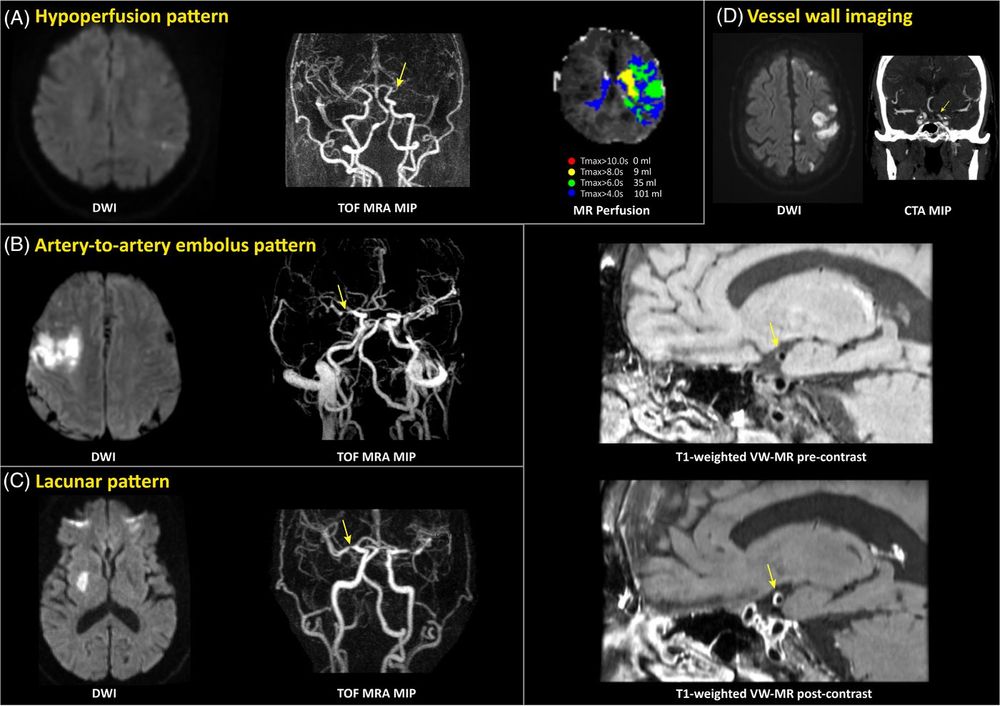

LAA usually causes either full-territory or embolic-appearing strokes confined to a single vascular territory. There are exceptions (such as athero-embolism “jailing” a small vessel causing a lacunar appearance) but this is a good rule of thumb.

LAA is diagnosed based on imaging characteristics, both of the stroke itself and the blood vessels. The latter is critical for management, meaning we need vessel imaging to work it up.

Options include:

- CTA (preferred)

- MRA

- Carotid ultrasound